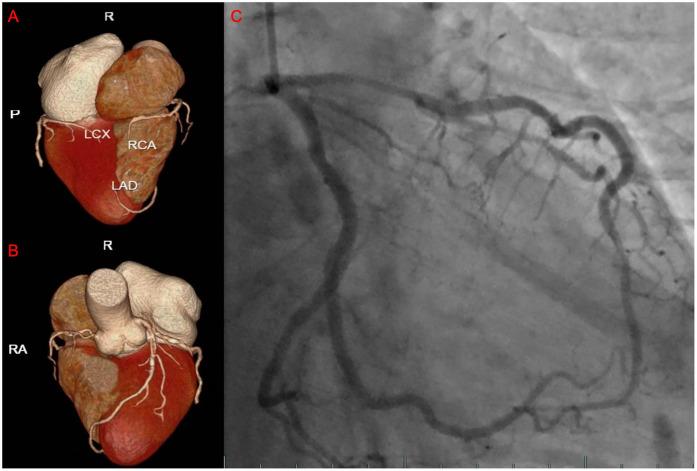

This report presents a rare case of Takotsubo cardiomyopathy (TTS) triggered by envenomation from . Following the snakebite, the patient rapidly developed severe pain and bleeding at the bite site, and subsequently experienced acute chest tightness and chest pain during hospitalisation. To elucidate the aetiology, the patient underwent a series of investigations, including electrocardiography, transthoracic echocardiography, and coronary angiography, which ultimately confirmed the diagnosis of TTS. The patient received comprehensive treatment comprising administration of anti-venom serum to neutralise the venom, fluid resuscitation, and antiplatelet therapy. The clinical condition gradually stabilised, and the patient was eventually discharged in good health.

本报告呈现了一例罕见的由 咬伤引发应激性心肌病(TTS)的病例。被蛇咬伤后,患者咬伤部位迅速出现剧痛和出血,随后在住院期间经历了急性胸闷和胸痛。为明确病因,患者接受了一系列检查,包括心电图、经胸超声心动图和冠状动脉造影,最终确诊为TTS。患者接受了综合治疗,包括注射抗蛇毒血清以中和毒液、液体复苏和抗血小板治疗。临床状况逐渐稳定,患者最终康复出院。